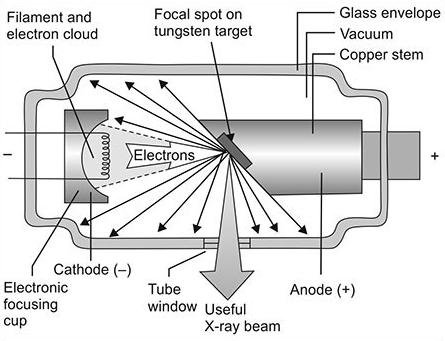

2. Radiation Safety

Radiation protection is a top priority. Choose a device that includes:

- FDA/CE/ISO certification

- Lead shielding or internal radiation protection

- Proper collimation to minimize scatter radiation